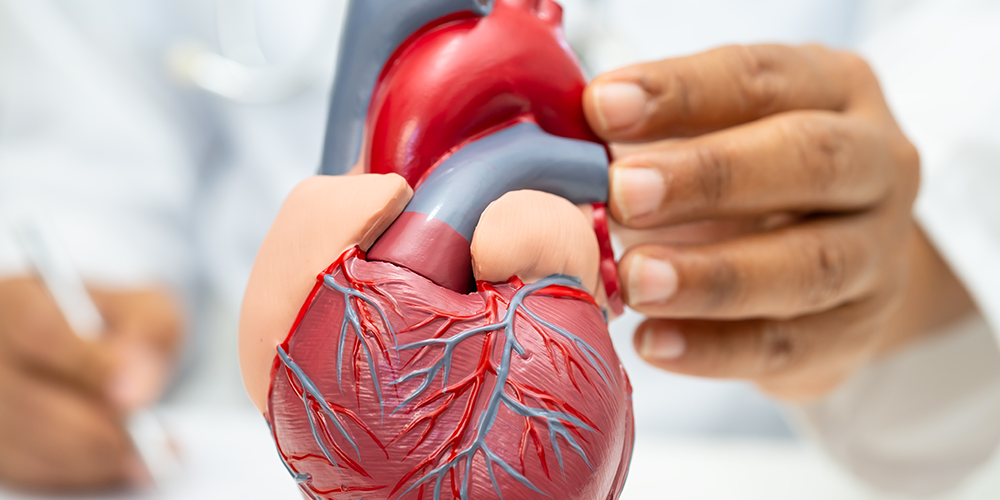

How Heart Disease Can Lead to Kidney Failure

Our human body is a perfectly balanced system in which every organ has its role that supports the others. The heart pumps blood, the kidneys filter waste, the brain controls function, and the liver supports digestion and immunity. Among all

Why Are Heart Attacks Increasing in Young Adults?

Introduction It was not long ago that heart attacks were a problem faced by older adults. It was rare that anyone younger than 30 suffered a heart attack. However, now 1 in 5 heart attack patients are young adults. It